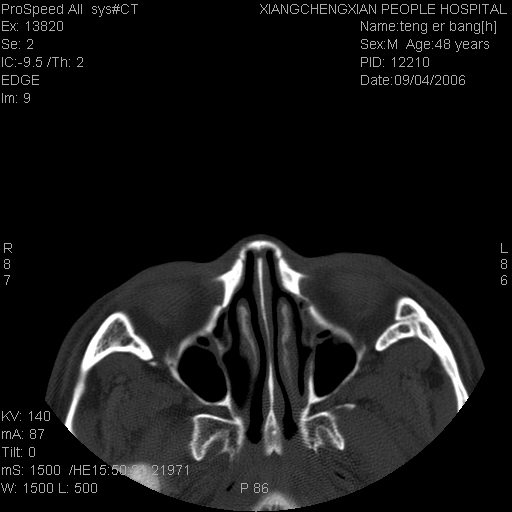

患者,男,以头面部外伤后头疼1小时为主诉入院,患者1小时前被他人打伤头部及左侧面部,眼睑无水肿,左侧面部肿胀压疼,未触及骨擦音。专科检查:耳鼻喉未见异常。

ct:平扫+冠扫:双侧鼻骨对比,冠扫s6#示右侧鼻骨尖部可见线状低密度影,边缘光滑,并见硬化.软组织未见肿胀.

诊断意见:鼻额缝(鼻骨与上颌骨额突缝),但个别同志认为是骨折.因此请同行们会诊.多谢了!